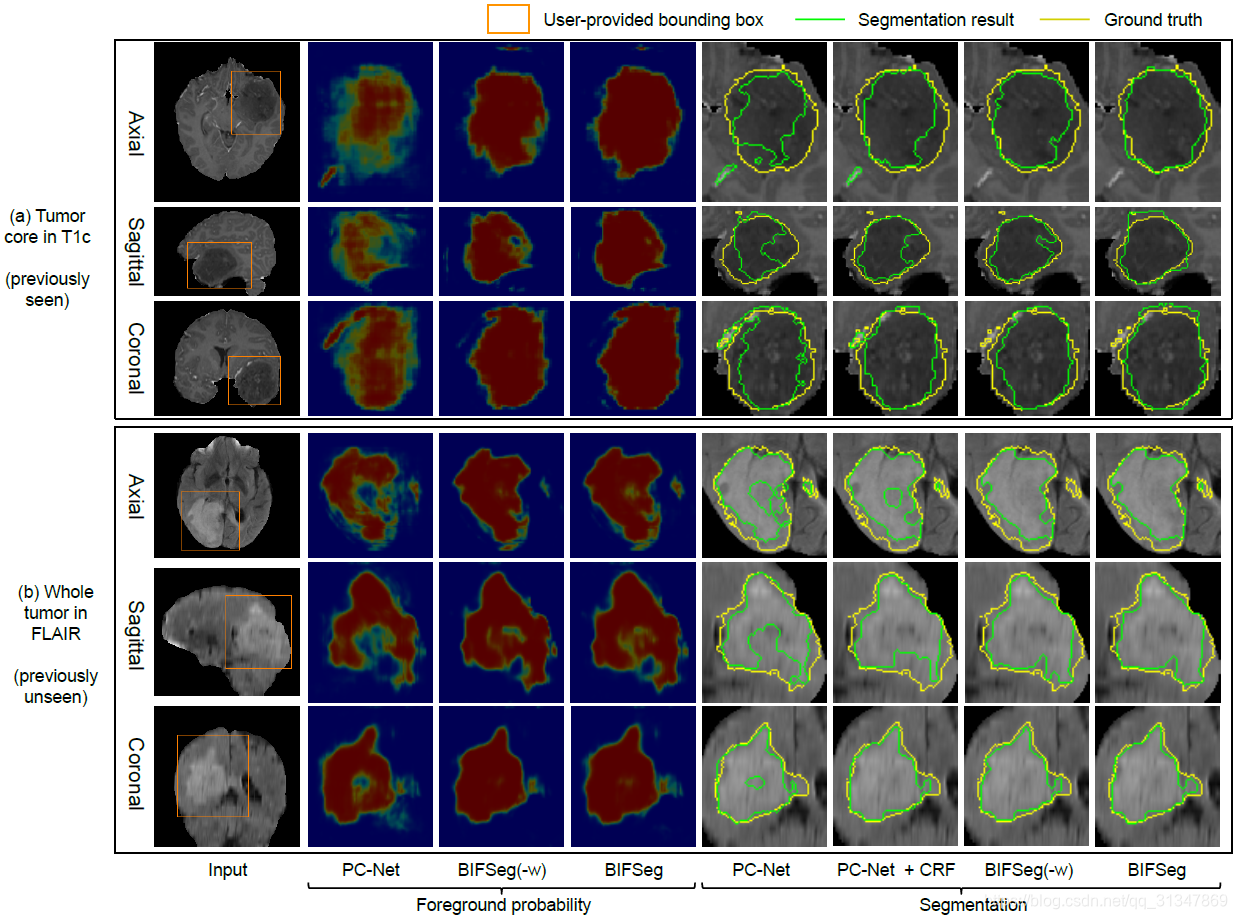

比较 BIFSeg 和 1)P-Net/PC-Net 的初始分割结果;2)用 CRF 处理之后的分割结果;3)BIFSeg(-w) 的分割结果(基于 Eq(1),所有像素的权重 w ( i ) = 1 w(i) = 1 w(i)=1),以及其他交互式分割方法:用于 2D 分割的 GrabCut,SlicSeg,Random Walks;用于 3D 分割的 GeoS,GrowCut,GrabCut 3D

(2)Unsupervised Image-specific Fine-tuning:

基于 PC-Net 得到的初始分割结果,仍然用其他三种方式进行无监督的调整。

不管对于见过的还是没见过的图像,BIFSeg 仍然是表现最好的,其他两种方法相比初始结果有提升,但是不够好。